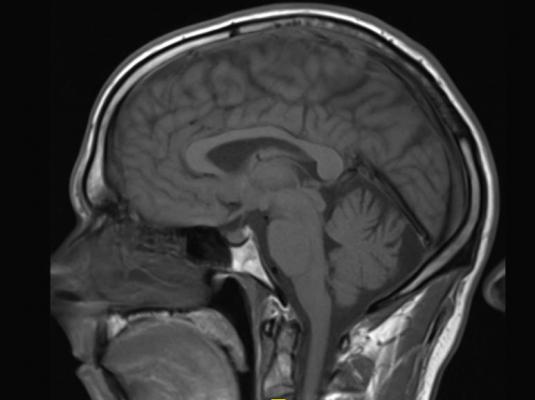

For the study, Riedy and colleagues used susceptibility-weighted imaging—a magnetic resonance imaging (MRI) technique that provides improved visibility of blood and is highly sensitive to hemorrhage—to evaluate 603 military service members with TBI. The median time from point of injury to imaging was 856 days. Of the 603 military service members who participated in the study, 7 percent were found to have at least one occurrence of cerebral microhemorrhage.

The study also supports previous claims that using susceptibility-weighted imaging to evaluate brain injury patients may be more effective than conventional MRI. In this study’s capacity, using susceptibility-weighted imaging resulted in detecting significantly more microhemorrhages due to a higher spatial resolution and signal, with 77 percent of cerebral microhemorrhages appearing more evident through susceptibility-weighted imaging when compared to conventional MRI.